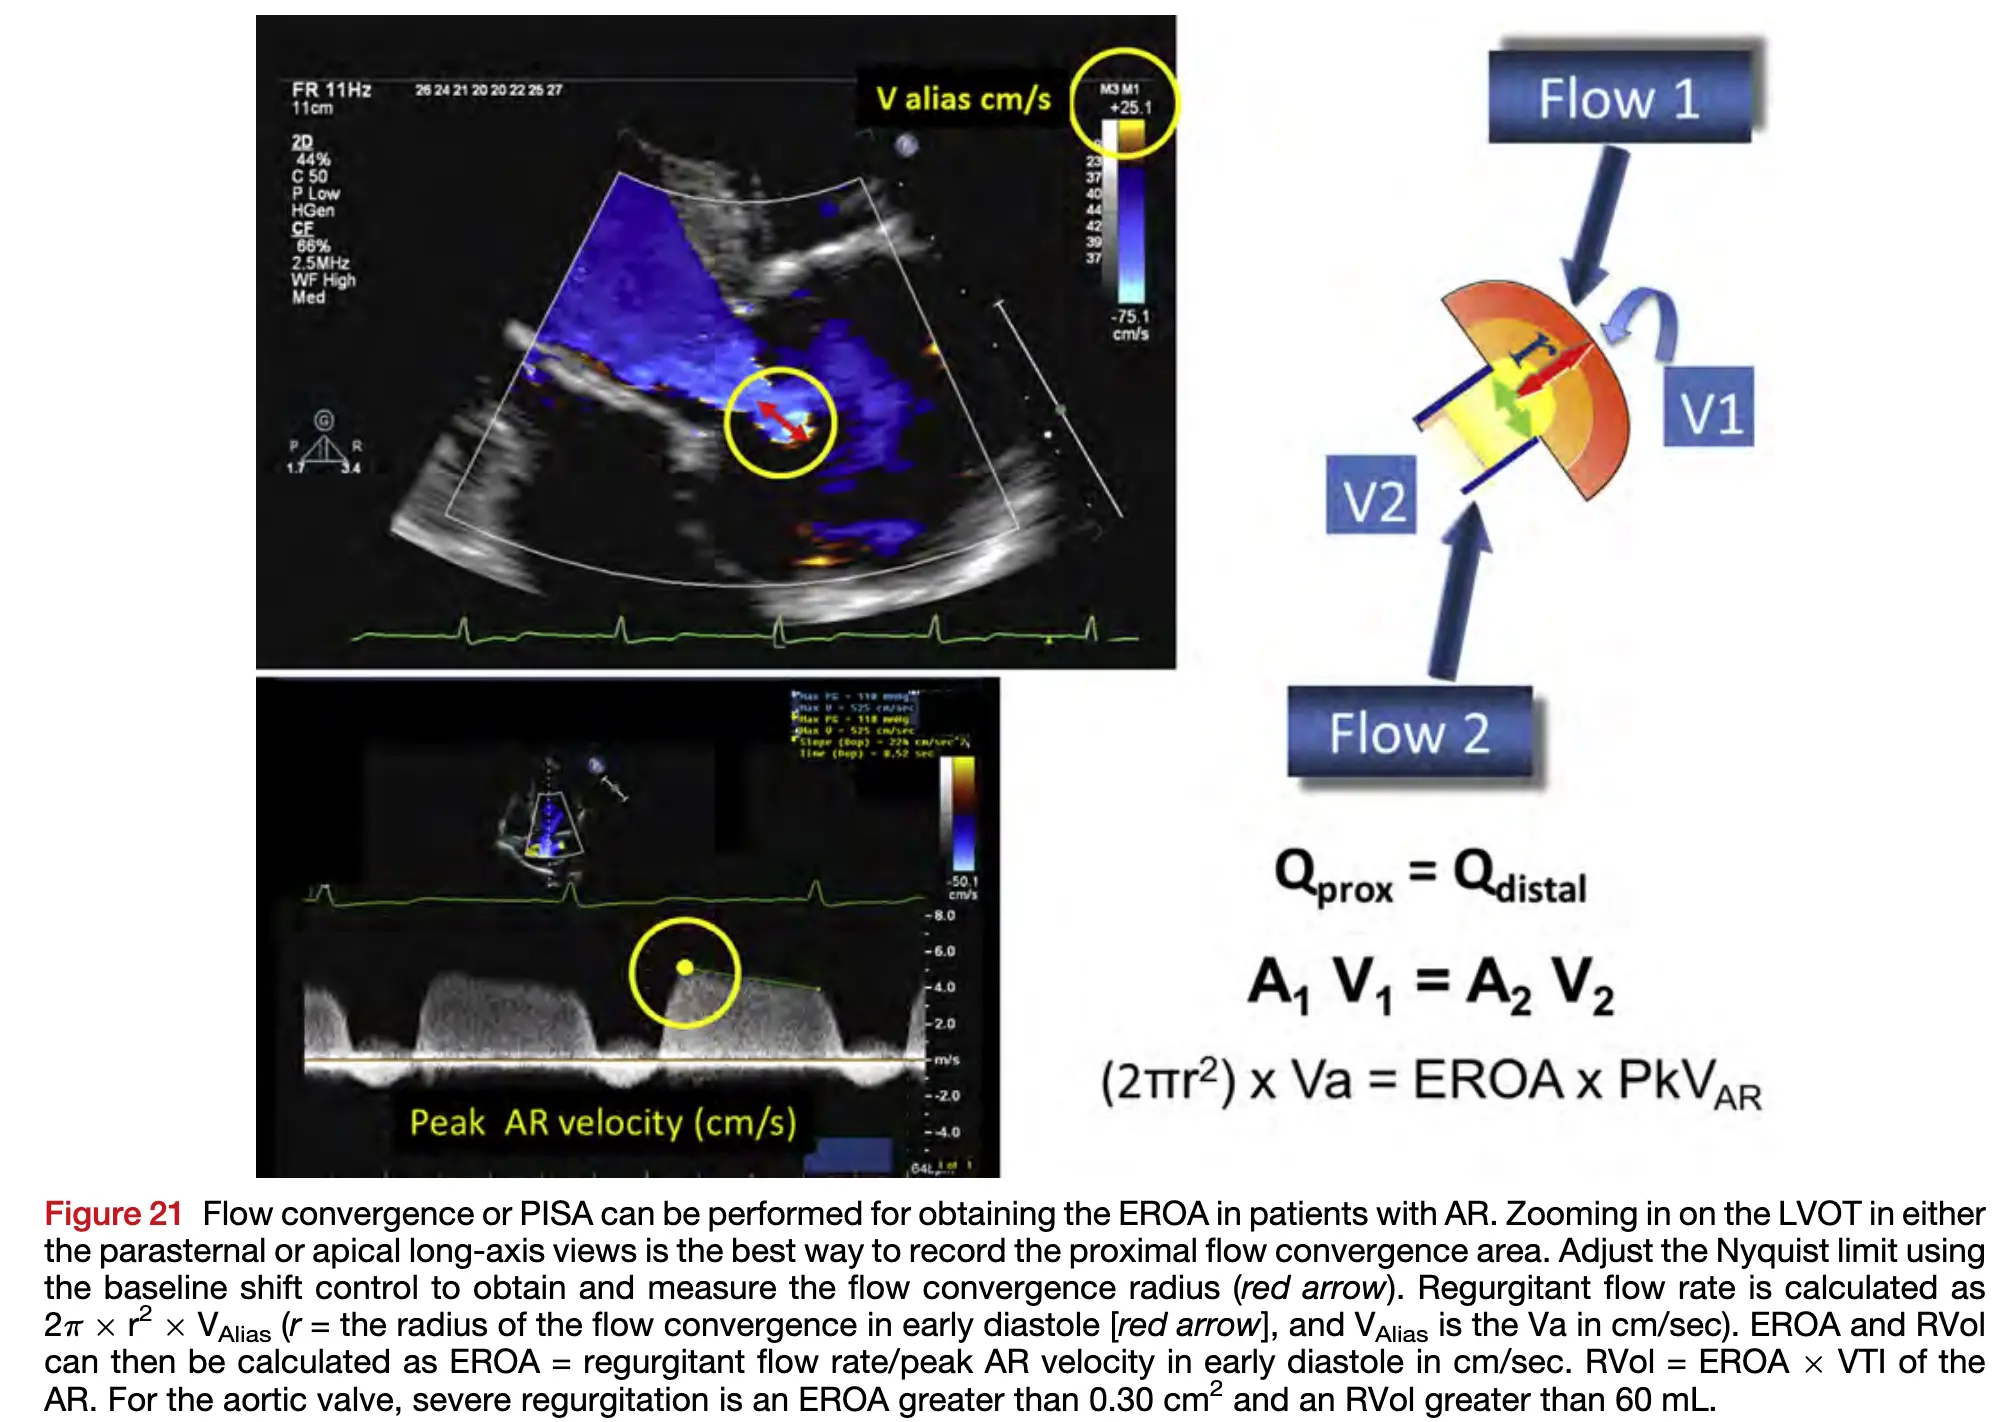

- Measurement of the AR peak velocity and VTI by CWD allows calculation of the EROA and RVol

- The threshold for severe AR is an EROA ≥0.30 cm^2 and an RVol > 60 mL